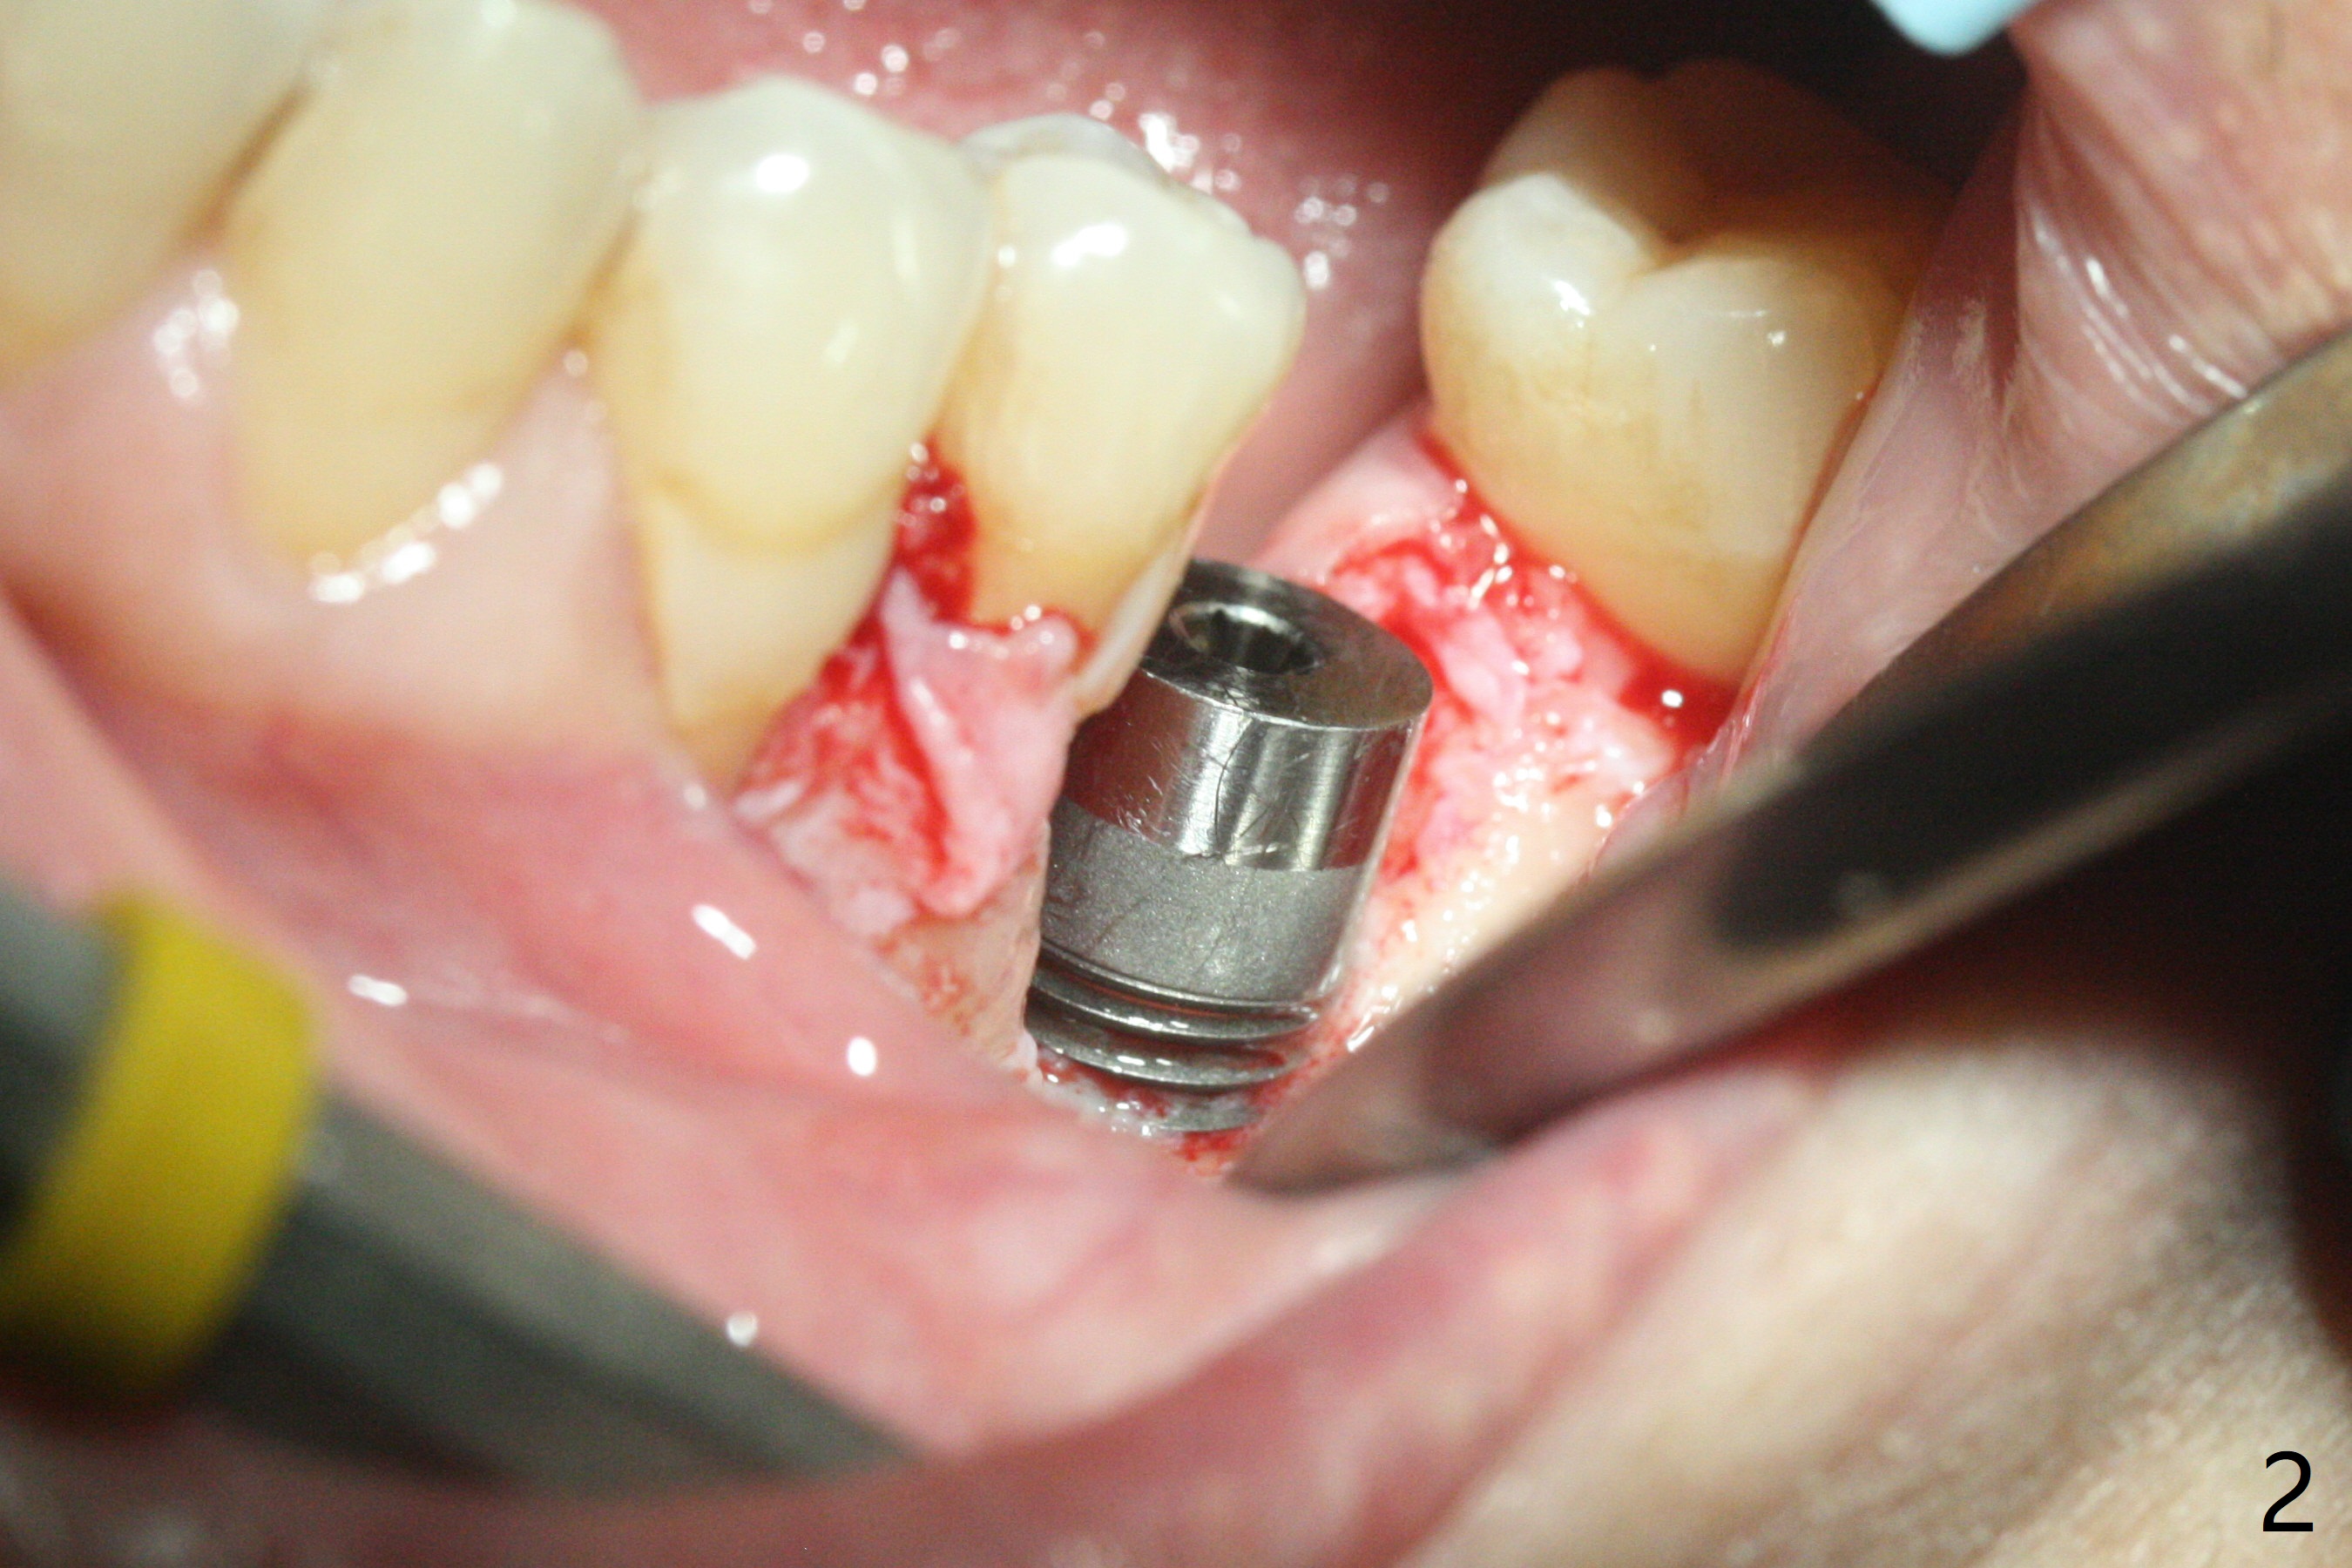

左下6植体周围炎诊断后两周,病人回来做植骨,服用抗菌素一周,炎症有所减轻,但口腔卫生不佳(图一)。软组织水平植体表面菌斑去除后,才切开,清除肉芽组织,钛刷(图二),双氧水擦洗,放置粘性骨粉(图三)和PRF膜,缝合,安置基台(图四:A),有利于牙周敷料固定。术后第二天病人汇报左下唇麻木,不肯用药;第六天回来(图五),麻木造成嘴唇创伤,同意服用Medrol Dosepak。